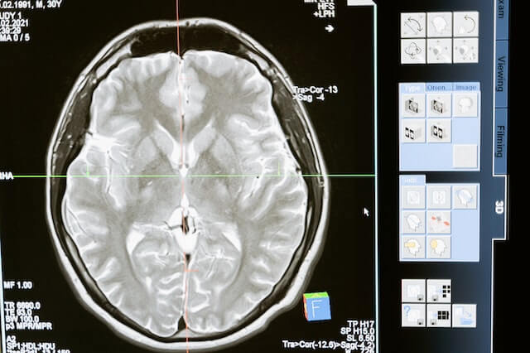

뇌졸증은 뇌혈관의 급작스러운 문제가 원인이 되어 뇌세포에 손상을 일으키는 질환입니다. 뇌졸증의 초기 증상을 알고 대처법을 알아두면 심각한 합병증을 예방할 수 있는 경우가 많습니다. 뇌졸증의 초기 증상으로는 첫째, 어느 한쪽 팔, 다리 또는 얼굴에 힘이 없어지거나 마비 증상이 나타납니다. 둘째, 말하기 어렵거나, 이해하거나 표현하는 데 어려움이 생깁니다. 셋째, 전혀 예고 없이 균형인지, 현기증 또는 현기증이 발생하며, 걷기 어렵거나 주위환경에 대한 인식이 떨어집니다. 넷째, 심한 두통이 생기며 동반되는 고통이 생깁니다. 그리고, 뇌졸증의 초기 증상을 발견한 경우 다음과 같이 대처해야 합니다. 첫째, '빠른 대응'이 무엇보다 중요합니다. 병원을 즉시 찾아 전문의의 진단을 받아야 합니다. 뇌졸증은 치료가 늦어질수록 뇌세포에 일어난 손상이 커질 수 있기 때문입니다. 둘째, 병원에 도착하기 전 119나 가까운 응급실에 전화하여 상황을 설명하시기 바랍니다. 전문 의료진이 즉각적인 조치를 취할 수 있도록 사전에 준비하게 됩니다. 셋째, 긴장을 늦추고 호흡을 조절하시기 바랍니다. 긴장이 심해지면 혈액순환에 영향을 주어 상황을 악화시킬 수 있습니다. 마지막으로, 뇌졸증 초기 증상을 다른 사람에게도 알려 줍니다. 이를 통해 뇌졸증의 위험성을 알리고, 빠른 대처가 가능해질 것입니다. 뇌졸증 초기 증상을 알고 대처법을 습득함으로써 효과적인 조치를 취할 수 있으며, 더 많은 사람들이 뇌졸증으로 인한 불행한 상황을 피할 수 있습니다.